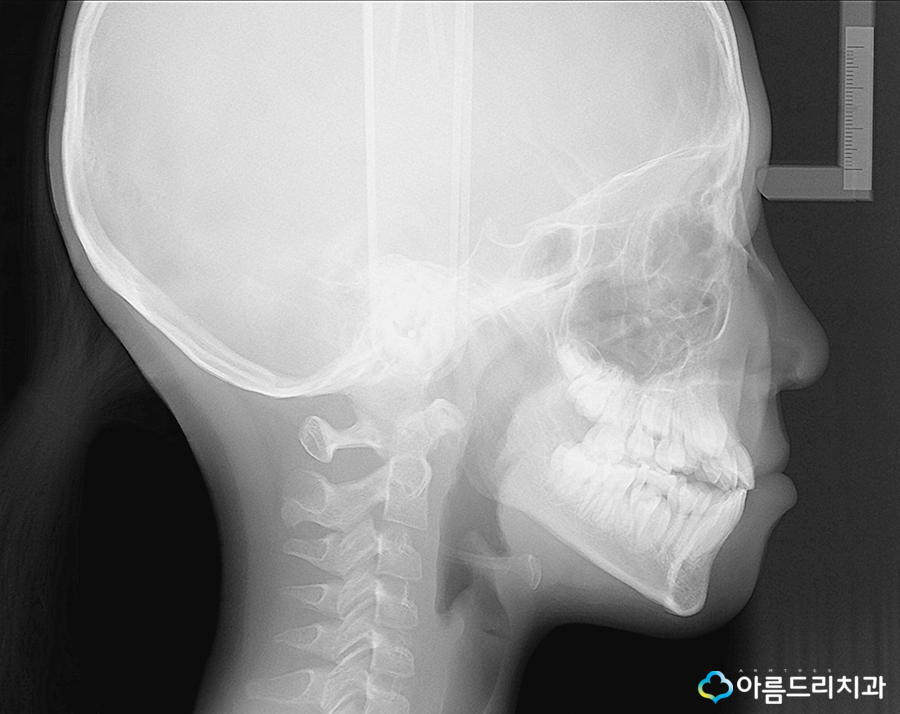

어린이치아교정을 할 때 성장 및 치아와 골격 진단을 보다 정밀하게 하기 위해 두부방사선 사진을 촬영하게 되는데요~ 이는 위턱과 아래 턱의 교합관계와 치아관계 등의 골격적인 문제 를 확인하는 용도로 쓰이고 있으며 이를 통해 골격 문제에 대한 분석과 계획을 세우게되죠.

위의 두가지는 성인교정과 어린이부정교합의 경우 마찬가지로 채득하게 되는 자료입니다.

성장기의 아이들을 위한 어린이부정교합 및 치아교정을 위해서는 성장판검사를 하는데요.

앞서 설명드린것과 같이 어린이 교정치료에 있어 시기가 너무 빠르거나 그 시기를 놓치게 되면 성장을 이용한 골격교정이 힘들어 질 수 있기 때문에 가장 적절한 시기의 치아교정을 계획하기 위해 성장판검사를 시행하고 있어요.